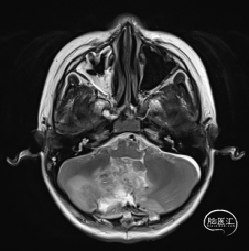

术后MRI

枕下后正中开颅小脑肿瘤切除术

术后病理